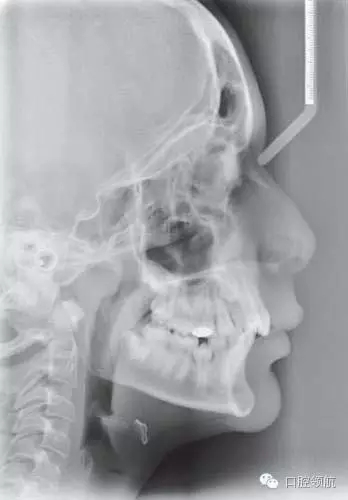

圖2.43顯示的是該患者的頭側(cè)位片,請總結(jié)其錯牙合情況

● 13歲男性患者,I類關系,輕度骨性II類,均面型。

● 雙側(cè)磨牙I類關系,中線齊,雙側(cè)尖牙1/2牙尖II類關系。

● 另外伴有:

○ 1. 異位UR3。

○ 下頜第二前磨牙阻生。

○ 深覆牙合。

○ 上下牙列均存在擁擠。

● 骨性因素:輕度骨性II類畸形,下頜后縮,并導致尖牙1/2牙尖的II類關系。

● 牙 牙合的異常發(fā)育:UR3異位發(fā)育,隨著其萌出,UR3有可能與UR4發(fā)生異位。單側(cè)異位是包含遺傳及環(huán)境因素在內(nèi)的多因素共同引起的。

● 牙-牙槽:牙量骨量不調(diào)引起了牙列擁擠,下切牙扭轉(zhuǎn),UL3唇側(cè)異位,下頜第二前磨牙的舌側(cè)阻生。

● 局部因素:下頜第二乳磨牙早失誘使錯牙合畸形發(fā)生,并導致LL5阻生,以及LR5的萌出障礙。

評價軟組織側(cè)貌及其和治療方案的關系

軟組織側(cè)貌豐滿。鼻唇角在90°~110°之間,上唇略靠前,唇紅飽滿。上下唇厚且健康。頦唇溝相對較深。總的來說,軟組織側(cè)貌是可以接受的,并且在拔牙內(nèi)收后仍不失美觀。